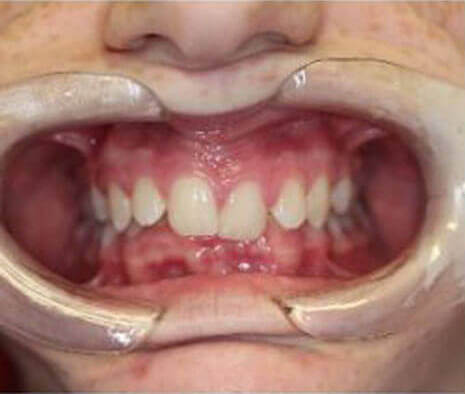

BEFORE

AFTER

Orthodontic treatment with braces, followed by implant to replace missing upper right lateral incisor and composite veneer on upper left lateral incisor.